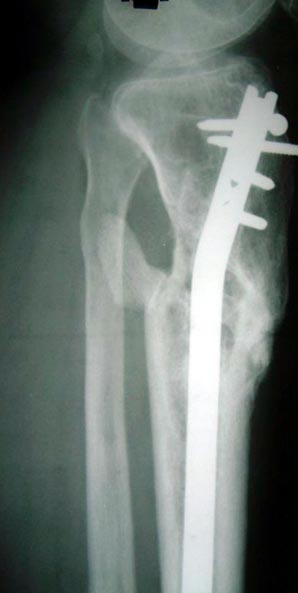

病例二 患者男性,45岁,胫骨上段开放粉碎骨折2年,骨不连

图2-1病例二、患者男性,45岁,胫骨上段开放粉碎骨折2年,骨不连。我们用带锁髓内钉固定骨折端提供支撑力,患者自体骨髓细胞经与松质骨和骨生长因子复合,使没有细胞的植骨材料变成了有细胞的活骨。骨折在9个月后愈合。